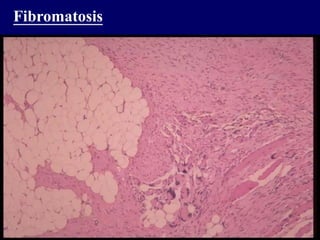

Fibromatosis

 Fibroproliferative lesions

 Desmoid - Infiltrative masses

in abdominal, extra-abdominal

& intra-abdominal

 Fibroblasts & Myofibroblasts

 Palmar, plantar fibromatosis

 Surgical excision

Beta-catenin/ AFP gene mutation

 Infiltrative growth pattern

 Tendency to recur

Fibromatosis  Fibroproliferative lesions Desmoid - Infiltrative masses in abdominal, extra-abdominal & intra-abdominal  Fibroblasts & Myofibroblasts  Palmar, plantar fibromatosis  Surgical excision Beta-catenin/ AFP gene mutation  Infiltrative growth pattern  Tendency to recur